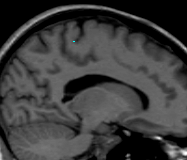

Trace the Central Sulcus in the sagittal view. Select a medial sagittal slice where the “dots” from the sulci lines drawn in the axial view are visible. Trace this sulcus inferiorly to the corpus collosum (Fig 7-8).

Figure 7                  Figure

8